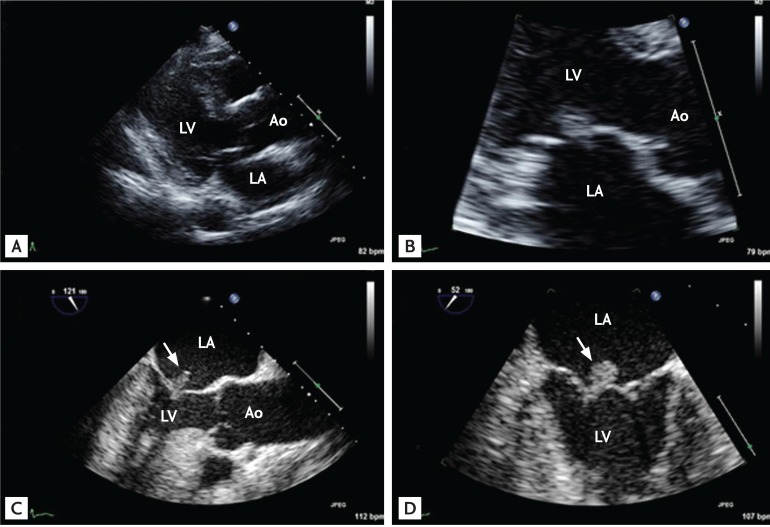

Figure 3

Representative echocardiographic images of a patient with non-nosocomial healthcare-associated infective endocarditis involving an apparently normal-looking valve. The patient, a 60-year-old female, was on maintenance hemodialysis for end-stage renal disease due to diabetes. She visited the emergency department due to fever and general weakness. A blood culture showed Enterococcus faecium bacteremia. Compared with her previous echocardiographic images, which showed an apparently normal-looking aortic valve (A, B), follow-up echocardiography showed typical vegetation (C; arrow) with aortic regurgitation (D). Ao, aorta; LA, left atrium; LV, left ventricle.